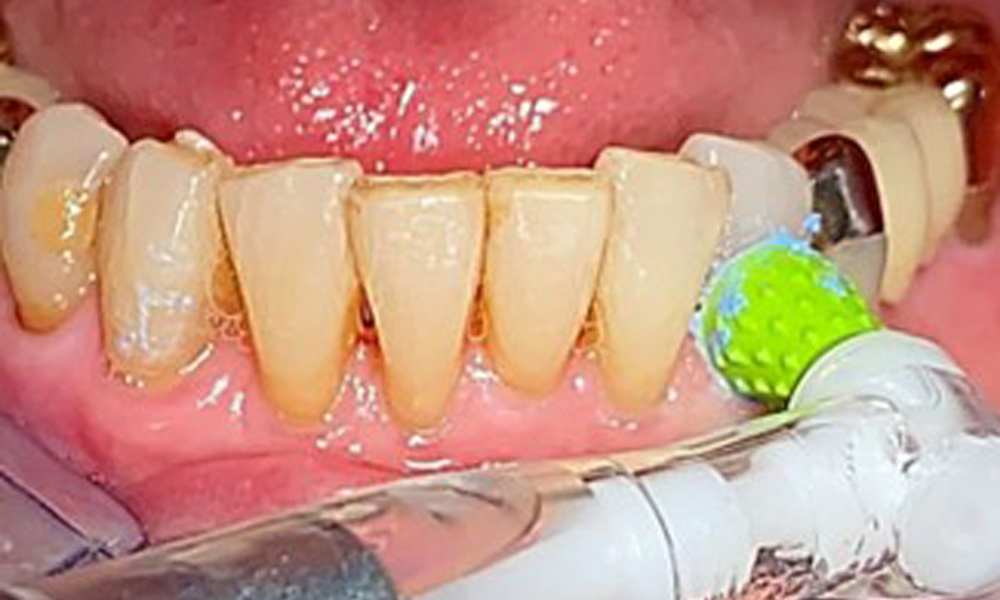

An air polishing system should be used with low-abrasive powder to remove biofilm from the restoration margins, interdental areas and implant surfaces (Fig. 12). Selective polishing (Fig. 13) should be used to smooth any less sensitive areas, as this decreases bacterial reattachment (9).

Selective polishing of tooth 33 (Proxeo Twist, W&H, shown here)

Fig. 13: Selective polishing of tooth 33 (Proxeo Twist, W&H, shown here)